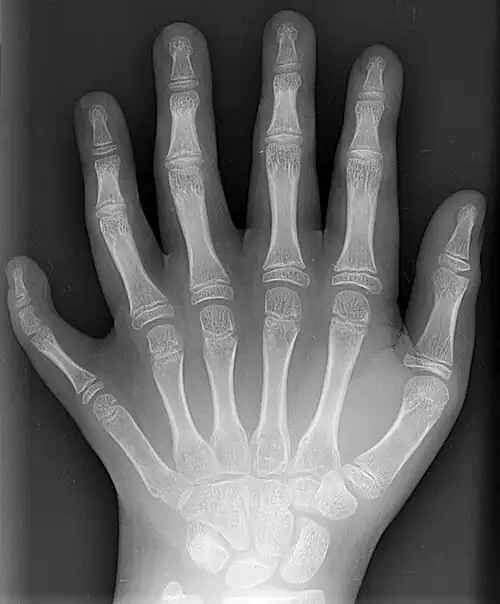

Bones

The skeleton of the human hand consists of 27 bones:[10] the eight short carpal bones of the wrist are organized into a proximal row (scaphoid, lunate, triquetral and pisiform) which articulates with the bones of the forearm, and a distal row (trapezium, trapezoid, capitate and hamate), which articulates with the bases of the five metacarpal bones of the hand. The heads of the metacarpals will each in turn articulate with the bases of the proximal phalanx of the fingers and thumb. These articulations with the fingers are the metacarpophalangeal joints known as the knuckles. At the palmar aspect of the first metacarpophalangeal joints are small, almost spherical bones called the sesamoid bones. The fourteen phalanges make up the fingers and thumb, and are numbered I-V (thumb to little finger) when the hand is viewed from an anatomical position (palm up). The four fingers each consist of three phalanx bones: proximal, middle, and distal. The thumb only consists of a proximal and distal phalanx.[11] Together with the phalanges of the fingers and thumb these metacarpal bones form five rays or poly-articulated chains.

Additional images

X-ray showing joints -

Hand bone anatomy